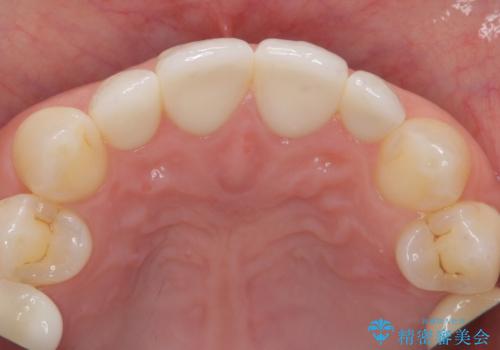

隣の前歯が小さいため、4本被せてバランスをとりました。

4本セラミックにすると大きさだけでなく、色も揃えられるのでおすすめです。

歯の向きは悪くなかったため、神経は取らずに治療しました。